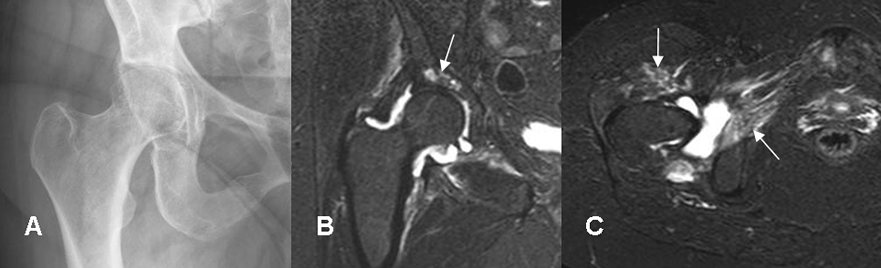

Fig 54. Artritis séptica.

A: Rx AP. Sin cambios significativos en el espacio. Hay pinzamiento mixto en la cadera.

B: RM coronal y C: RM axial en STIR. Derrame articular, por artritis infecciosa. En B hay cambios inflamatorios en la cavidad acetabular y en C en los músculos vecinos.

En la fase subaguda hay erosiones óseas e irregularidad de las superficies articulares por destrucción del hueso subcondral y disminución del espacio articular, por daño del cartílago. La aparición de reacción perióstica indica osteomielitis asociada. (20, 21). (Fig 54, 55 y 56).